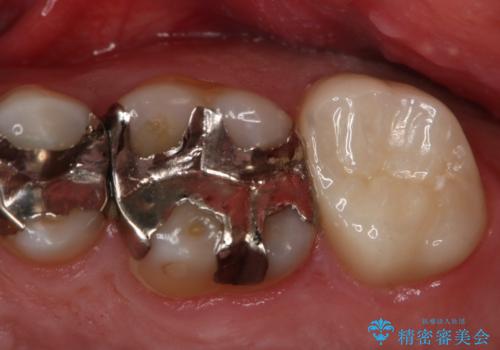

- 右上6番の銀歯をセラミックに変えたいと希望された患者様です。

切削量、形態を考慮し、セラミックインレーでの治療を計画しました。

銀歯と虫歯を除去した上でCRで裏層し形態を整えて印象を行っています。